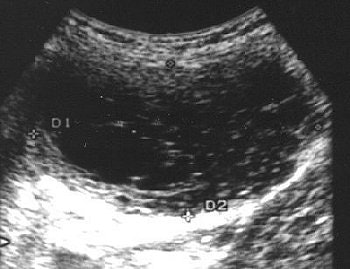

The patient -- who had no previous genitourinary disease -- presented with abdominal fullness, menstrual irregularities, and an enlarged uterus. A transabdominal ultrasound revealed a left cornual, myometrial complex cystic mass with smooth borders.

| Axial transabdominal pelvic sonogram shows complex myometrial mass with cystic and solid components. |